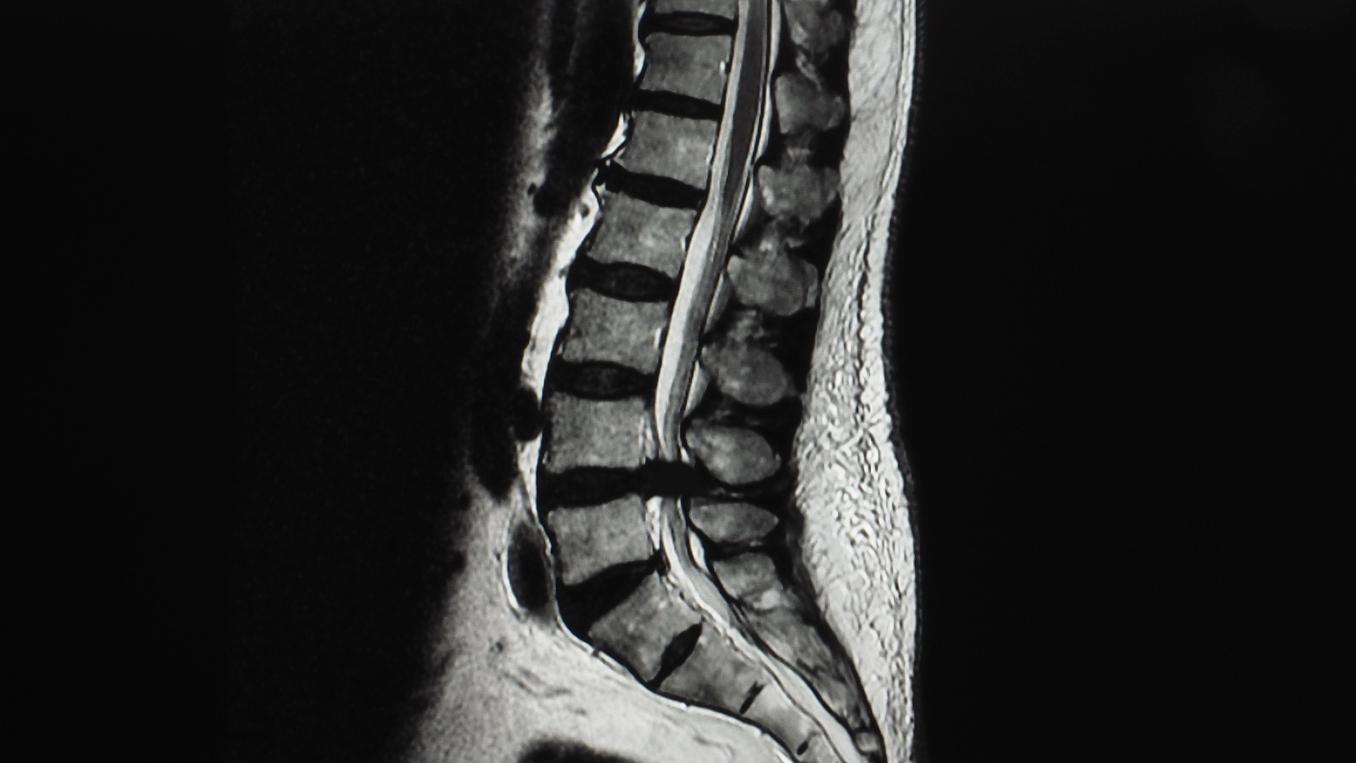

The scientific program delved into the latest advancements in chiropractic treatment for headaches and chronic head and neck pain. On August 30, attendees participated in presentations and workshops focusing on these issues The following day shifted its focus to the cervical spine, covering surgical aspects, MRI imaging, and recent research on cervical spine manipulation